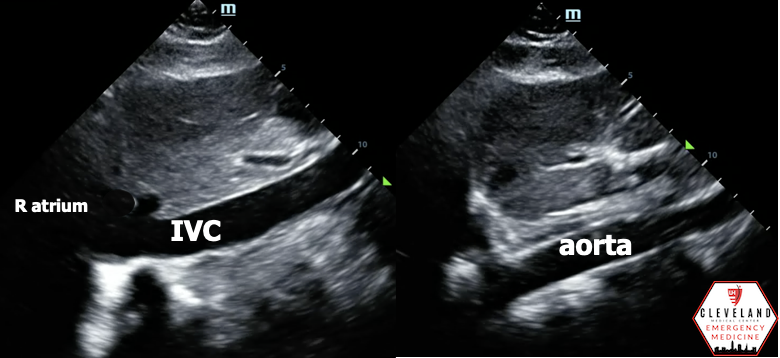

Transverse IVC/Aorta View (standard aorta views but focusing on IVC)

• From the longitudinal view, rotate probe 90 degrees so the probe marker is pointing toward the patient’s right

• Identify the vertebral shadow. Look for the IVC and aorta lying just above. IVC is always to the patient right and aorta to the left

Differentiate IVC from aorta

• IVC:

• Thinner walls

• Travels through the liver; parenchyma will be directly adjacent to the vessel* (see images below)

• Drains into the right atrium*

• Hepatic veins drain into it* (hepatic confluence)

• May see respiratory variation (collapsibility with inspiration)

• Lacks pulsatile flow on pulse wave doppler

• Won’t have sequential anterior branches in the abdomen like the aorta does (i.e. celiac, SMA)